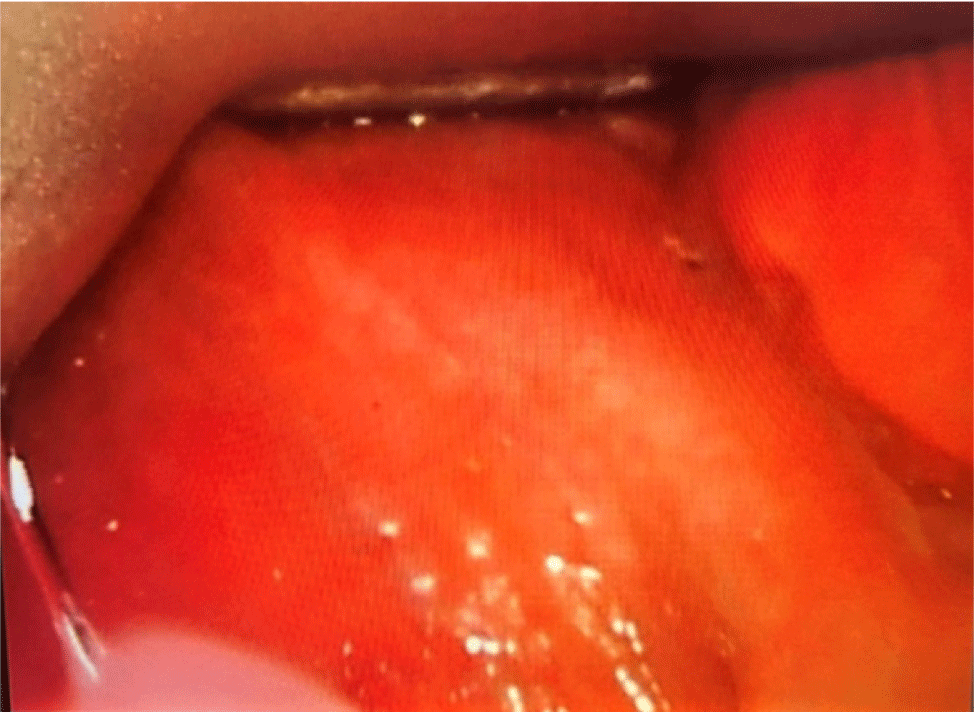

Premedication was administered with fentanyl 50 mcg, and 10% lidocaine spray (eight puffs) was applied to the oropharynx to facilitate airway examination. A C-MAC video laryngoscope was used to assess the airway in both supine and lateral positions, revealing a Cormack-Lehane grade IV view (Fig. 4).